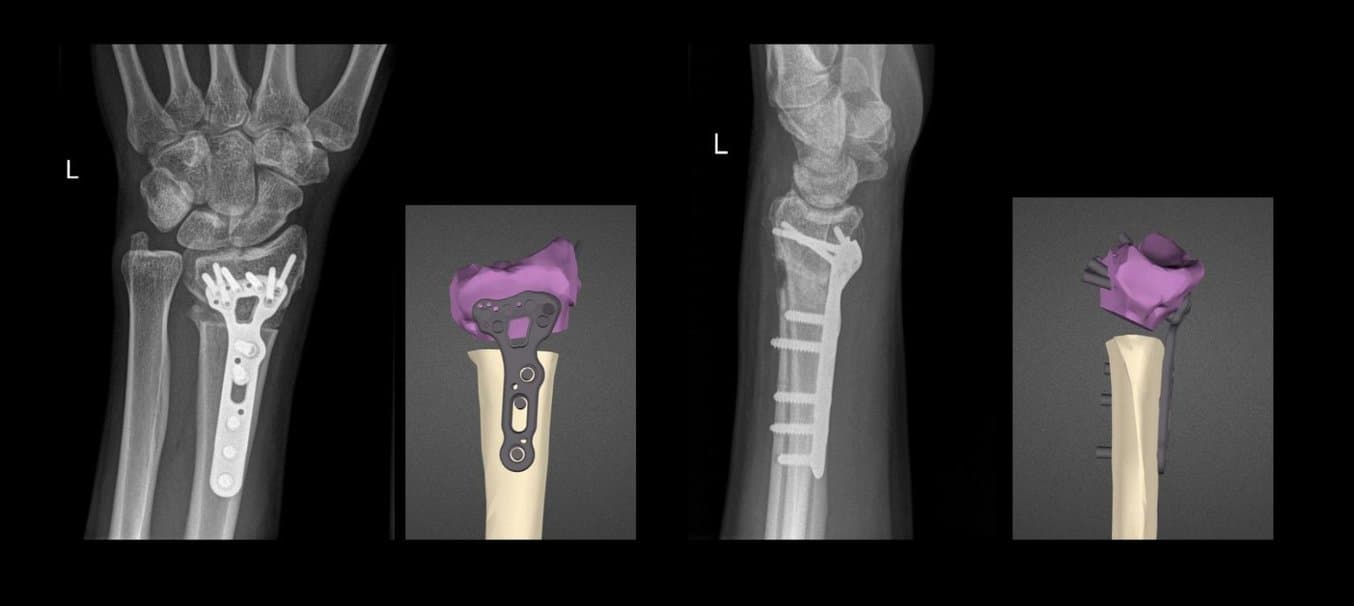

3D-gedruckte patientenspezifische Knochenmodelle und Chirurgieschablonen aus Nylon 12 Powder zur Behandlung einer distalen Speichenverformung.

Fehlverheilung eines distalen Speichenbruchs, 3D-Planung des Behandlungsergebnisses und Röntgenergebnisse zwei Wochen nach der OP